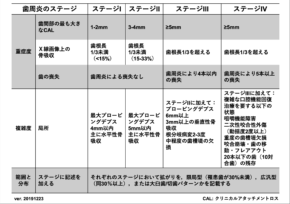

上記は、日本歯周病学会の歯周病の新分類の指標になりますが、

『歯周病の重症度』をステージ分類し

『歯周病の進行のスピード』をグレード分類します。

少し難しいお話かもしれませんが、診断は人によって違うため、患者様一人一人の状態に合わせて治療方針と治療計画を立てる必要性があるということです。